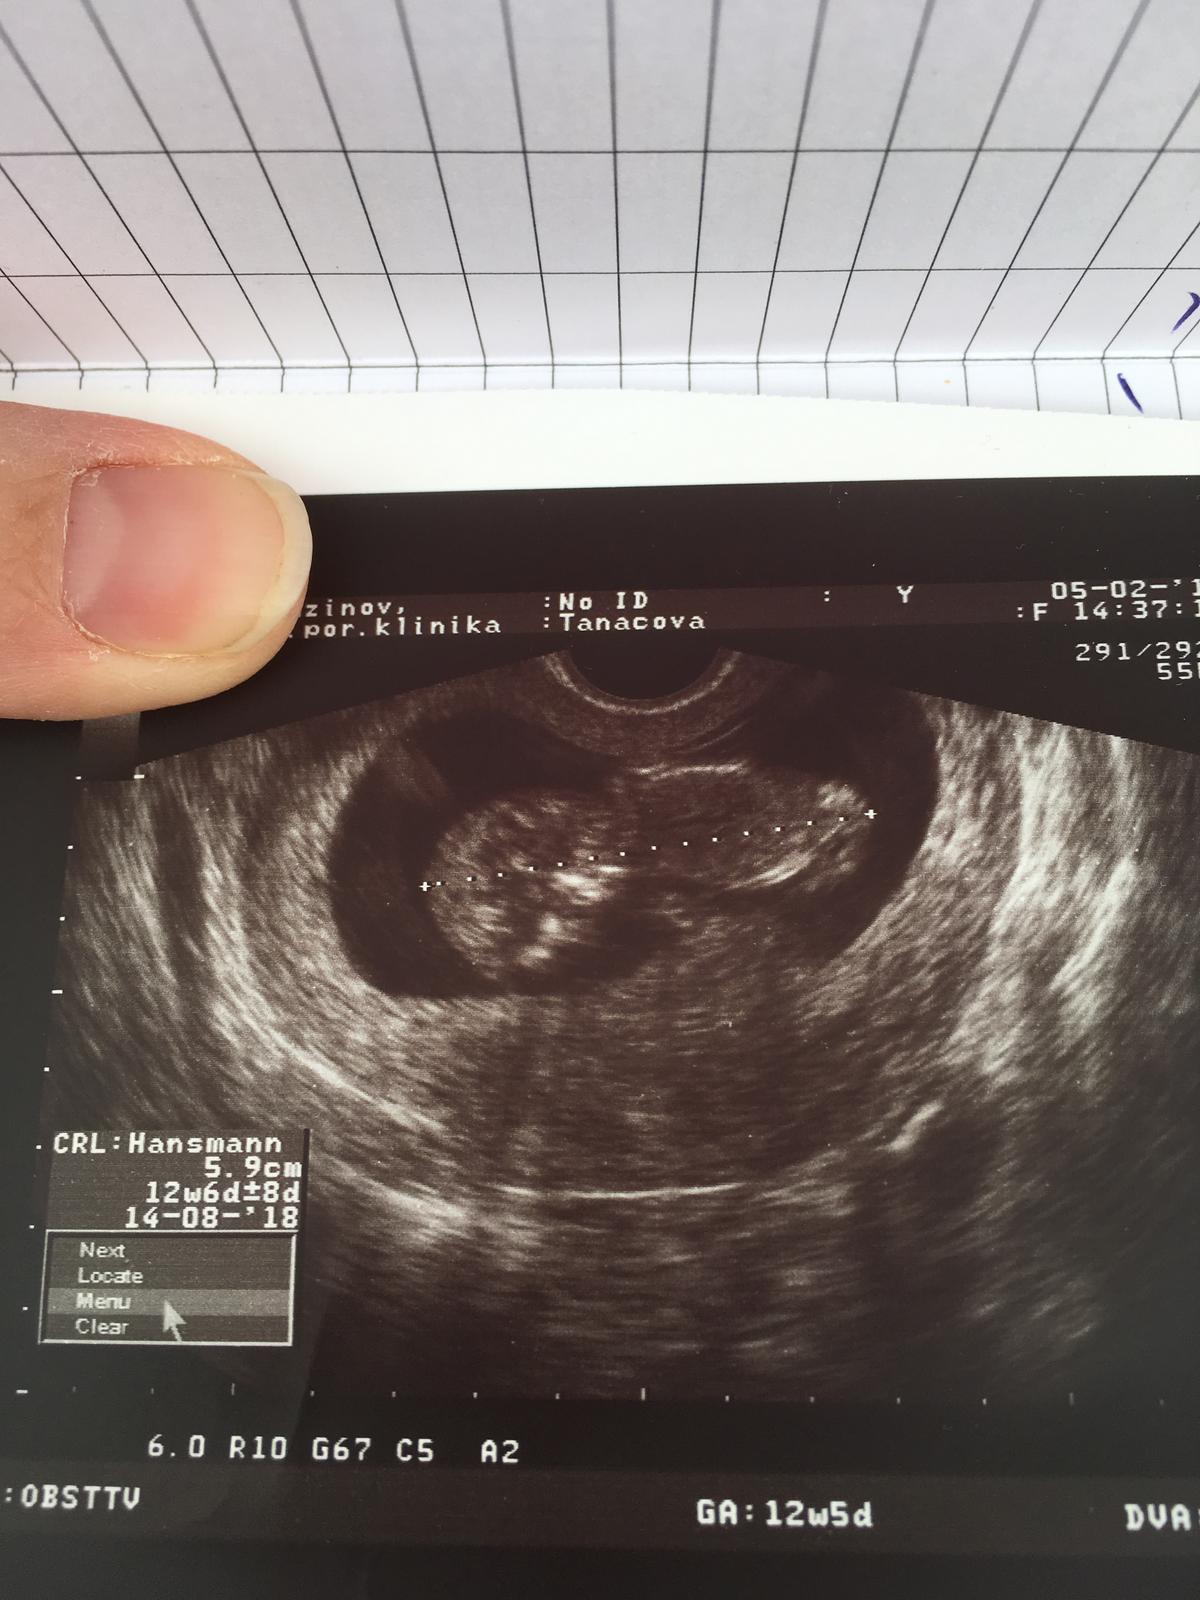

Ahojte, už dlhšie vás pozerám, v októbri minulého roku som mala biochemické tehu, potom som mala cyklus všelijaký, až minulý bol 29 dní. Užívam progesteron. Minulý mesiac som bola na folikulometrii 16DC a nevyzeralo to, že by ovu prebehla preto mi lekárka povedala, že tento mesiac začneme s clostilbegytom. Pre istotu som si urobila test, 28DC je práve dnes

Progesteron som vysadila v nedelu ako vždy po 10-tich dňoch, vrchný test je z včera večera, spodný dnes ráno